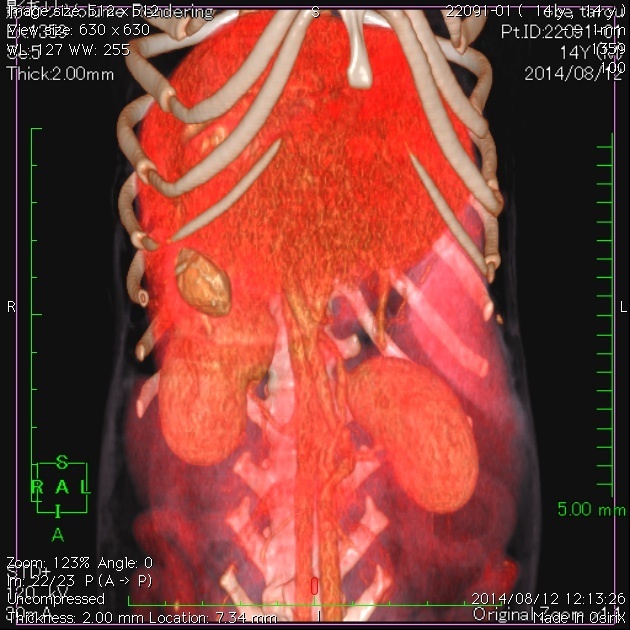

CT検査では膵臓にしこりは見つからなかったので、とりあえずは一安心だったんですが・・・。CT検査で胃の中に大きな種があることが分かりました。

上の画像はCTの断層の画像ですが、下の画像は3D校正したCT画像です。見事に種が写ってますね。一番下は内視鏡で摘出しているタネです。胃内異物はとても多い病気ですが、胃内にある場合は、よほど大きくなければ手術ではなく内視鏡で摘出しています。